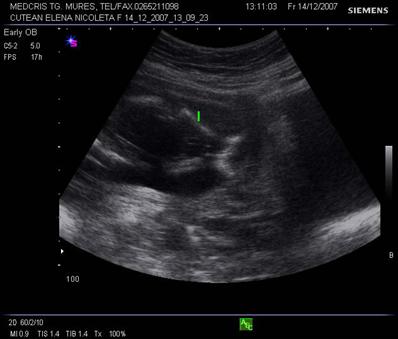

Aspecte normale ecografice in trimestrul II si III de sarcina

In cursul trim II, bolta craniana apare ca bine definita, hiperecogena, elipsoidala. Suturile si fontanelele trebuie recunoscute ca fiziologice si nu trebuie confundate cu defecte structurale craniene.

Linia de mijloc hiperecogena frontoocipitala este formata anterior si posterior de falx cerebri si fisura interemisferica, central de septum pellucidum. La sfarsitul primului trimestru de sarcina, linia de mijloc hiperecogena este flancata la distanta de o pereche de ventriculi laterali, ce inconjoara plexurile choroide ecogene. Din saptamana a 15-a cresterea cortexului devine vizibila, la marginea ventriculilor laterali, ca o margine hipoecogena. Partea posterioara a ventriculilor laterali ramane ocupata de plexurile choroide, in timp ce coarnele anterioare contin doar fluid. Dupa saptamana 19-a ventriculii laterali au caractere constante pe tot parcursul sarcinii.[1,3,8,13,14]